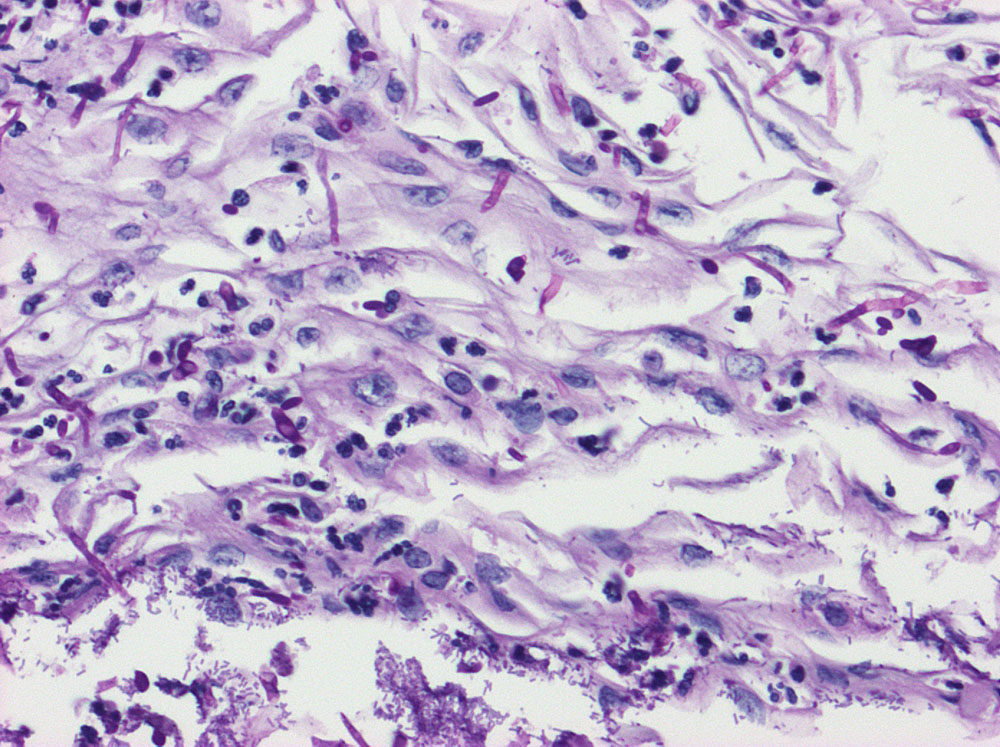

Akute Soorösophagitis und bakterielle Ösophagitis

Das oberflächliche Plattenepithel der Ösophagusschleimhaut ist diffus durchsetzt von Soorpseudohyphen und Sporen sowie sehr zahlreichen Stäbchenbakterien. Wenig neutrophile Granulozyten.

50 jährige HIV positive Patientin, CDC3. Soorösophagitis. HSV? CMV?

Der Nachweis von Pseudohyphen ist Zeichen einer echten Infektion mit Soor (Gewebsinvasion). Der Nachweis von Sporen allein rechtfertigt nicht zur Diagnose einer Soorösophagitis (Mundflora). Eine bakterielle Ösophagitis liegt vor, wenn zahlreiche Bakterien das Gewebe invadieren. Diese tritt fast immer nur bei Immunsuppression auf. Der Nachweis von Bakterien an der Oberfläche von Ulzera entspricht hingegen eher einer Kolonisierung. Bakterien können sekundäre Pathogene bei einer viralen oder fungalen Infektion des Ösophagus darstellen.